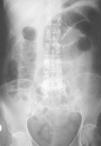

Mujer de 54 años, sin antecedentes de interés, que acude por presentar desde hace 2 días dolor en hemiabdomen superior tipo cólico acompañado de vómitos fecaloideos de 12 horas de evolución. Exploración física: afebril, destaca un abdomen doloroso, distendido y timpánico con aumento de los ruidos hidroaéreos, el resto sin hallazgos de interés. La analítica de sangre (hemograma, bioquímica básica y hemostasia) presenta una leucocitosis (12.900 leucocitos, 86,1% neutrófilos), el resto de los valores están dentro de la normalidad. Radiografía simple de abdomen (fig. 2): dilatación de las asas de intestino delgado y edema de pared. Radiografía en bipedestación (fig. 3): niveles hidroaéreos. Se realiza laparotomía exploradora ante el cuadro de obstrucción de intestino delgado, hallándose serositis segmentaria en yeyuno con restos larvarios de AS. Tras instaurar sueroterapia y dieta absoluta se produce una mejoría de su estado general en las siguientes 72 horas, con desaparición del dolor abdominal, reiniciándose la alimentación oral que tolera sin complicaciones. Ante el antecedente epidemiológico de ingesta de boquerones en vinagre 48 horas antes de la intervención, se realizaron tests cutáneos que fueron positivos para AS y negativos para la batería de pescados de consumo frecuente; así como niveles de IgE total (267 UI/ml; normal < 200) y específica para AS (44; normal < 0,35 RU/ml). La paciente fue diagnosticada de anisakiasis intestinal, se repiten las determinaciones de IgE cada 3 meses, normalizándose sus valores de IgE total despues de un año y permaneciendo elevada la IgE específica (15 RU/ml).

Figura 3. Radiografía de abdomen en bipedestación.